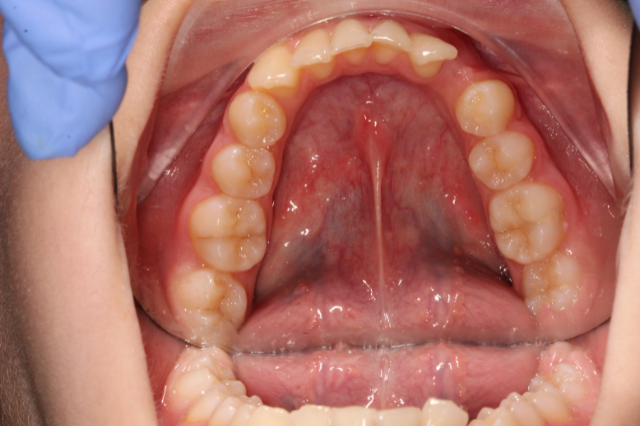

Fogív rendezés

A frontfogak torlódását és a harapás eltérését sikeresen korrigáltuk, így a fogív szabályossá vált, a rágófunkció javult és az esztétikai megjelenés is sokkal harmonikusabb lett.

Fogiv-rendezes-elott

Fogiv-rendezes-utan

Előtte

Utána